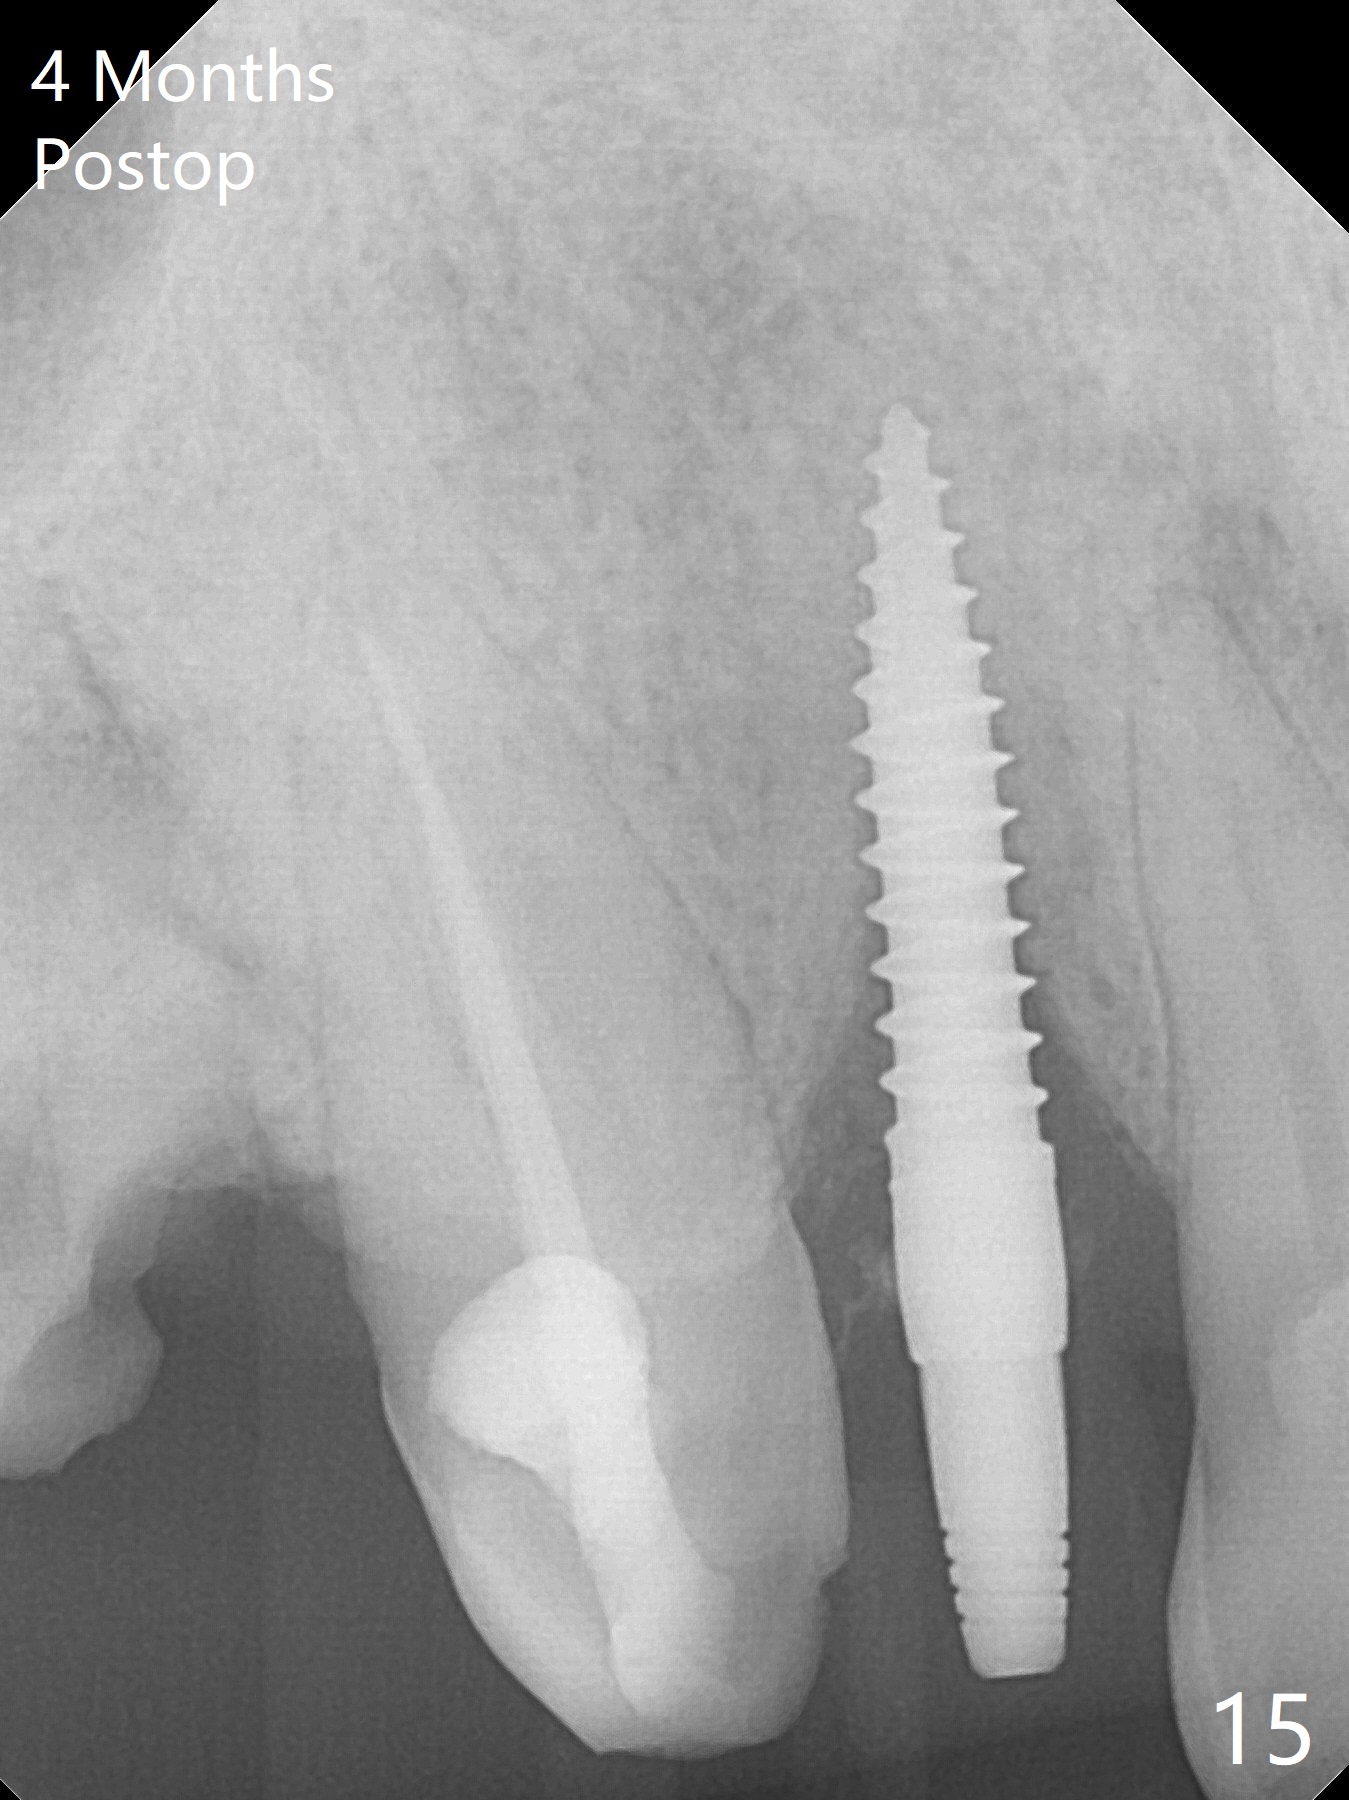

An apical abscess is present when the patient returns for immediate implant at #7 (Fig.1 *); a 2nd challenge is deep bite. After smooth extraction, the apical buccal plate is found to be perforated. Following debridement, a piece of gauze is placed in the apical defect for hemostasis, while osteotomy is initiated palatal (Fig.2). The apical defect seems to be extensive (Fig.3 yellow dashed line). A new trajectory is intended (red arrow) without much success. Before implant placement, bone graft is placed in the apical defect defect area, while a drill (Fig.4 D) is inserted in the finished osteotomy (Fig.5 O). In spite of seemingly large apical defect, the buccal crest bone exists (Fig.4 x). A 3x14(2) mm 1-piece implant is placed with stability; the first round of bone graft is apparently around the apical portion of the implant (Fig.6 *). The coronal end of the implant has to be adjusted several times buccopalatally to accommodate the deep bite. A 2nd round of bone graft following an immediate provisional closes the coronal space of the socket (Fig.7 *). CT will be taken to show the bone graft to repair the buccal plate defect when the patient returns for postop follow-up. In fact the defect is minimal in CT a month ago. The fistula does not disappear 1 week postop, but it is non tender (Fig.8). The patient complains of asymptomatic swelling in the right nostril. CT shows that the large buccal perforation is repaired with large amount of bone graft (Fig.9,10 *). It would be nicer to place the implant slightly more buccal apically (Fig.11 red lines; Fig.12 (preop design)). The buccoapical fistula disappears nearly 1 month postop (Fig.13). The apparently "lifeless" bone graft seems to be harmonious with the surrounding tissue (Fig.14). The periimplant gap reopens with implant mobility nearly 4 months postop (Fig.15), which is related to micro-movement associated with the immediate provisional. The latter is removed. A larger 2-piece implant will be placed in a 2-staged manner if needed (Fig.16). In fact the 3x14 mm straight 1-piece implant (Fig.17) has no mobility when it is retightened, but the trajectory remains buccal. Incision shows that there is no implant thread exposure. A 3x14 mm 15 degree angled 1-piece dummy implant is able to establish the correct trajectory, but there is no occlusal clearance (Fig.18). Micromovement during osteointegration may recreate loosening. Finally using Lindamann bur, the osteotomy is changed so that a 3.5x13 mm 2-piece implant does not need an angled abutment to establish occlusion (Fig.19). There is one palatal thread exposure. Allograft is placed circumferentially, followed by Human Amnion-Chorion Allograft and Collagen Plug. The wound does not heal 8 days postop (Fig.20), as related to the age (79 years old)? The wound appears to heal with a membrane on the surface (Amnion-Chorion one?) 3 weeks postop (Fig.21). The ridge looks wide 3.5 months postop (Fig.22,23). A 4.5x5.5(3) mm appears to be seated incompletely with a gap between the abutment and the implant (Fig.24<). A provisional is fabricated after heavy palatal reduction. Two months later, the provisional fractures. After repositioning the abutment with complete seating and torque (Fig.25), impression is taken. Although the buccal plate is concave, the gingiva remains healthy 10 months post cementation (Fig.26,27).